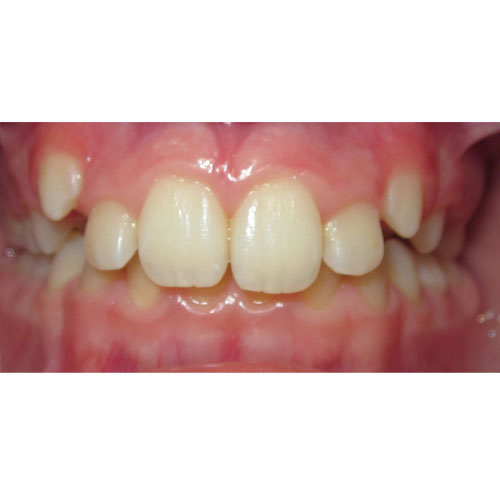

Nasze rezultaty